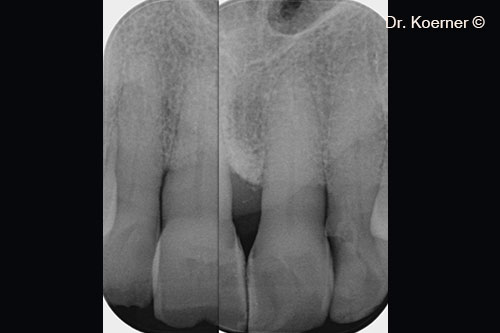

Localized periodontal defect 11

Pocket probing 9mm

Initial x-ray